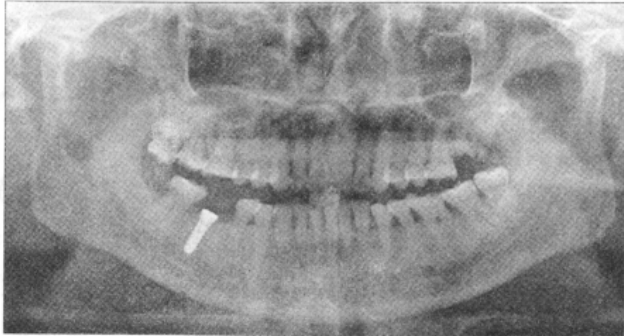

阿替卡因肾上腺素注射液(必兰)局部麻醉下行右下第一磨牙牙槽嵴顶切开,翻瓣至骨面,逐级备洞,植入Straumann种植体1枚(标准美学颈部,直径4.1mm,长度12mm),骨缺损处植入骨粉,旋入愈合基台(穿龈高度为3mm)后拉拢缝合,穿龈愈合,术后拍全口曲面断层片及牙科锥形束CT,术后检查发现下颌神经管内见骨折片突入,占管径约1/3,种植体根端离下牙槽神经管上缘约1.0mm。

箭头示种植体挤压致骨折碎片突入下牙槽神经管。